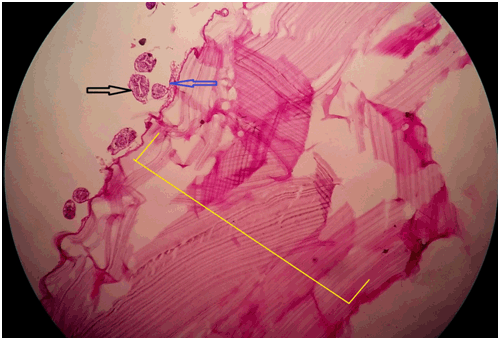

Figure 2: Histopathological image of hydatid cyst material showing scolices and capsule wall. [Black arrow: scolices, blue arrow: germinal layer of hydatid cyst, yellow line: hydatid cyst wall].

A case of 45-year-old female which was operated for laparoscopic cystostomy for single liver hydatid cyst (6×5 cm in right anterior lobe of liver, diagnosed by CECT abdomen). After four months of laparoscopic cystostomy, she was admitted in our hospital with complain of swelling and pain at the abdomen over previous laparoscopic port site scar. On per abdominal examination, there was a single 5×5 cm sized tender swelling at right hypochondrial port site scar with inflamed and reddish overlying skin. Ultrasonography (USG) scan of abdomen suggestive of 5×4×4 cm sized hypo echoic lesion with internal septation at the anterior abdominal wall at port site with extension to right sub diaphragmatic space with normal liver. Rest of biochemical and hematological investigation were normal. Initially, we suspected an abscess at port site, so we had planned for incision and drainage of material. But during operation, we came to know that the material resemble the endocyst and brood capsule of hydatid cyst. So we had removed all material and site washed with 0.5% cetrimide solution and flower tip malecot catheter inserted under USG guidance into the sub diaphragmatic extension. There was approximately 30 cc output from the malecot catheter for two days, and it was removed on fourth postoperative day. Wound at port site healed secondarily within two weeks. We had sent material for histopathological examination which was reveled hydatid cyst material (Figure 2).